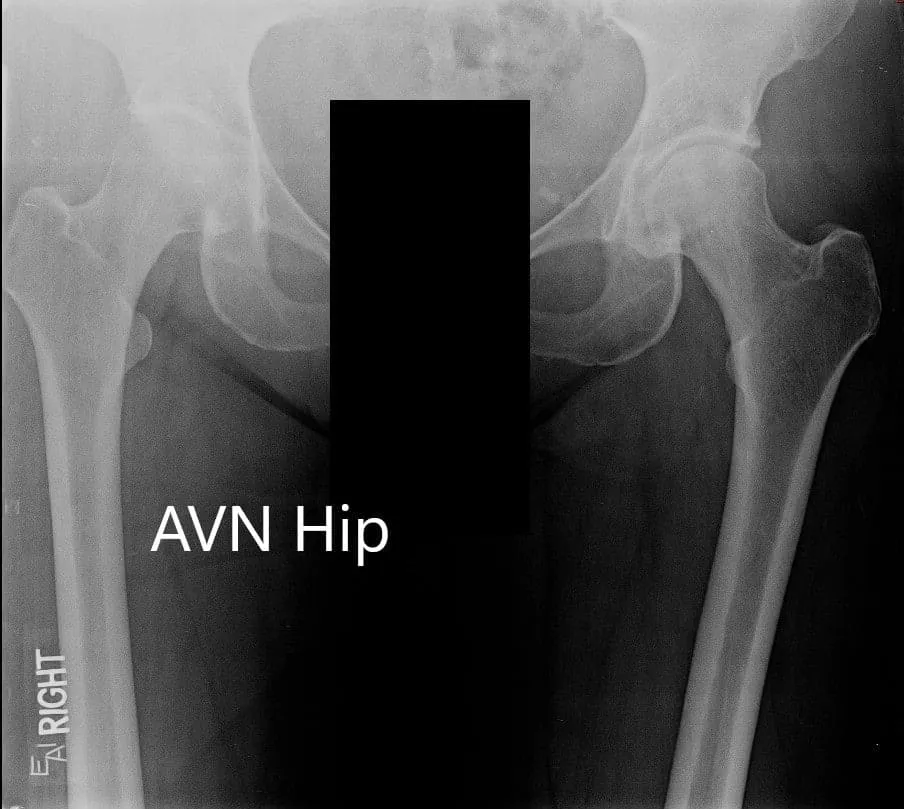

Imaging revealed osteoarthritic changes of the left hip with an AVN lesion that involves 60% of the femoral head. An MRI was obtained which revealed left femoral head avascular necrosis without overt subchondral collapse.

X-ray showing the AP view of the pelvis with both hip joints

X-ray showing the AP and frog-legged lateral views of the left hip joint